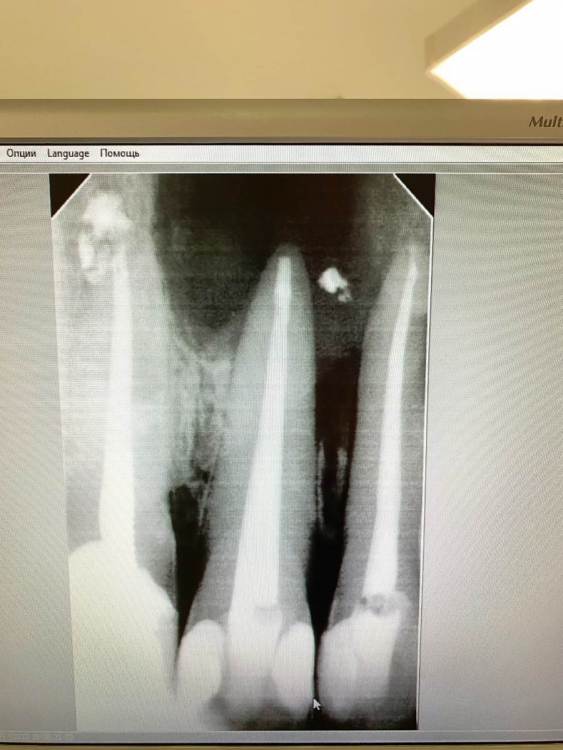

feGTX Опубликовано 15 июля, 2022 Поделиться Опубликовано 15 июля, 2022 (изменено) Здравствуйте. Очень нужна помощь стоматологов! В 2019 году обнаружил свищ над верхними передними зубами. Пошел к своему стоматологу, который начал следующее лечение: - нервы в зубах были удалены и пару дней я ходил с открытым каналом. Далее закладывался Метапекс, а потом постоянная пломба, но свищ не закрылся. 22 зуб также залечили. Были консультации и в других стоматологиях нашего маленького городка (КТ тогда тоже делалось), но в основном рекомендовали три зуба под удаление, закладывание искусственной кости, импланты или мосты на соседние зубы. Решили пробовать перелечивать со своим стоматологом. - 21 зуб снова вскрыли и несколько раз закладывали Кальцетин. Потом снова постоянная пломба. И свищ закрылся (это было осенью 2019 года). Далее делали несколько снимков - вроде медленно шло заживление. В сентябре 2021 года делал КТ нижней челюсти по другой проблеме, и захватилась верхняя челюсть - тоже были видны улучшения в сравнении с самой первой КТ. И вот на днях снова свищ на десне. Надавливаю под носом и выходит жидкость. Снимок сделали, но как-то коряво вышел он. Сделал также КТ. Снова всё плохо. Во вложении три старых снимка, один свежий, и несколько изображений с КТ. Если нужны еще какие-то срезы, то попробую сделать. Помогите пожалуйста. Изменено 15 июля, 2022 пользователем feGTX Ссылка на комментарий